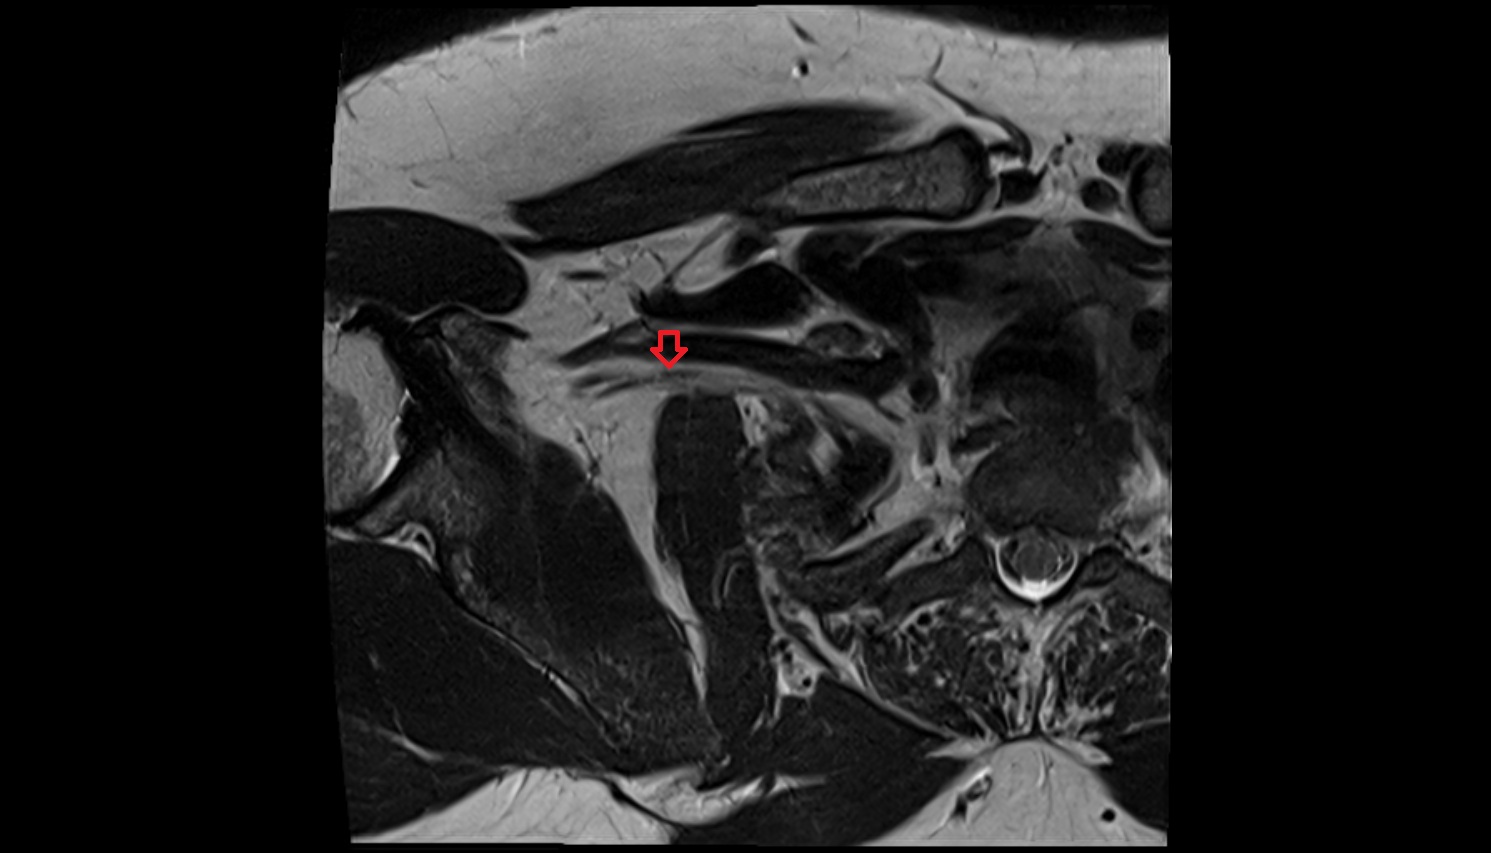

- Scapula

- Glenoid fossa

- Glenoid process of scapula

- Spine of scapula

- Acromion process of scapula

- Shoulder joint (glenohumeral joint)